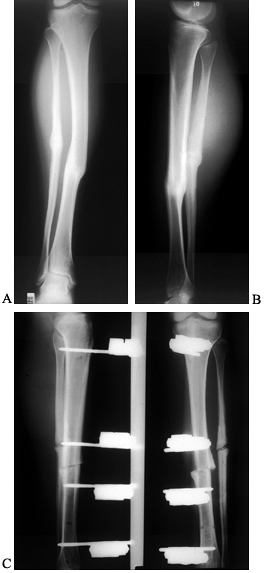

to assess the stability of the fixation construct. Radiolucency around

fracture callus (Fig. 135.1). Plain tomography

![]() |

Figure 135.1. A 27-year-old man sustained an open fracture of the shaft of the right femur secondary to a low-velocity gunshot wound. A: AP radiograph of the fractured right femur. B:

Postoperative AP radiograph. This wound was treated with irrigation and debridement, and immediate locked intramedullary nailing as well as parenteral antibiotics. C: Postoperative lateral radiograph. D: This fracture healed nicely, but 4 months later, the patient developed a localized abscess at the fracture site. This AP radiograph shows periosteal reaction at the healed fracture site. E: Lateral radiograph showing periosteal new bone at the fracture site. F: This was treated with incision and drainage of the abscess, removal of the intramedullary nail, cross-screws and reaming of the intramedullary canal to debride it, as well as administration of parenteral bactericidal antibiotics. This AP radiograph taken 4 months later shows the healed fracture with resolution of the bone infection. G: Lateral radiograph 4 months after debridement. |